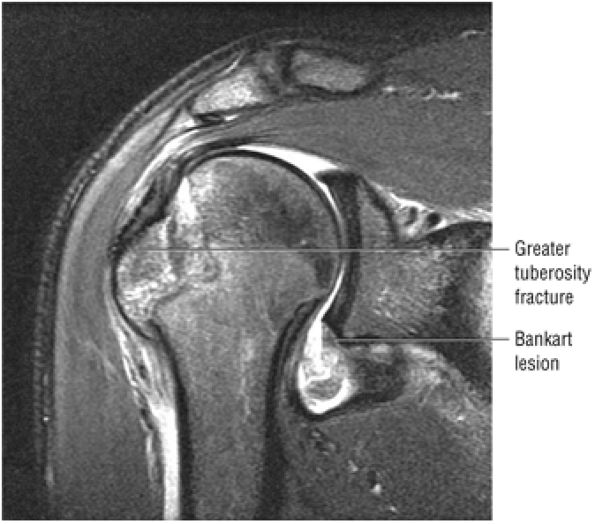

FIGURE 8.30 ● Axial images through the AC joint should be obtained on all shoulder MR examinations. (A) Axial T1- or PD-weighted images at this location are used to identify fractures of the distal clavicle and to demonstrate an os acromiale. (B) Axial FS PD-weighted images show cartilage covering the distal aspect of the clavicle and the medial aspect of the acromion at the AC joint. Cartilage defects and thinning, as well as subchondral bone marrow edema and cystic change, are evaluated on axial images through the AC joint. These degenerative changes can mimic the symptoms of a rotator cuff tear. (C) Axial T1- or PD-weighted images demonstrate the Hill-Sachs lesion of the humeral head, usually visualized as focal flattening or concave deformities in the posterolateral humeral head. The Hill-Sachs lesions is identified on the first or second superior axial image through the humeral head. Subcortical cystic change is more commonly visualized in the posterolateral humeral head and is usually an incidental finding in asymptomatic patients. (D) Axial FS PD-weighted images depict the biceps tendon coursing across the anteromedial aspect of the humeral head, within the rotator interval. This image location serves as a starting point for following the remainder of the biceps tendon into the bicipital groove on successive axial images moving from cranial to caudal. Tears of the supraspinatus and infraspinatus tendons are also identified at this image location on axial images. (E) Axial T1- or PD-weighted images allow evaluation of subcoracoid impingement. (F) In this location, thickening and increased signal in the superior glenohumeral ligament and coracohumeral ligament on an axial FS PD-weighted image may indicate adhesive capsulitis, particularly when accompanied by thickening and increased signal within the inferior glenohumeral ligament. (G) Axial T1- or PD-weighted images are used to identify subcortical cystic change in the greater and lesser tuberosity. This finding is commonly an indirect indication of abnormality or tearing in the overlying distal supraspinatus and subscapularis tendons, respectively. (H) Axial FS PD-weighted images through the proximal bicipital groove are used to identify “hidden lesions,” which are diagnosed when the biceps tendon is medially subluxing out of the bicipital groove, usually into a distal subscapularis tear or anterior to the lesser tuberosity. A degenerated biceps tendon may appear flattened and elongated as it rounds the lesser tuberosity into the proximal bicipital groove. Commonly, only the medial “tail” of the flattened degenerated biceps tendon subluxes out of the groove; the remainder of the flattened biceps tendon stays within the groove. (I) Axial T1- or PD-weighted images display the osseous glenoid subchondral surface, which should appear flat. Osseous glenoid remodeling, hypertrophy, deformity, subchondral cystic change, and edema are commonly identified as indirect evidence of overlying chronic cartilage degeneration or prior trauma. Posterior glenoid spurring may completely replace a degenerated or markedly attenuated posterior labrum. (J) Axial FS PD-weighted images are optimal for displaying the glenoid and humeral head cartilage. Chondral fissures, thinning, and defects are visualized when viewing successive cranial-to-caudal images through the glenohumeral joint. The anterior and posterior labrum are also optimally visualized and are normally firmly adherent to the glenoid and glenoid articular cartilage. (K) Axial T1- or PD-weighted images are used to identify bony Bankart lesions. These lesions are seen on inferior axial images through the glenohumeral ligament as oblique fracture lines extending through the anterior inferior glenoid. (L) Axial FS PD-weighted images show the prominent anterior band of the IGHL, which is occasionally mistaken for a tear of the anterior inferior labrum when fluid is interposed between the anterior band and the normal labrum.